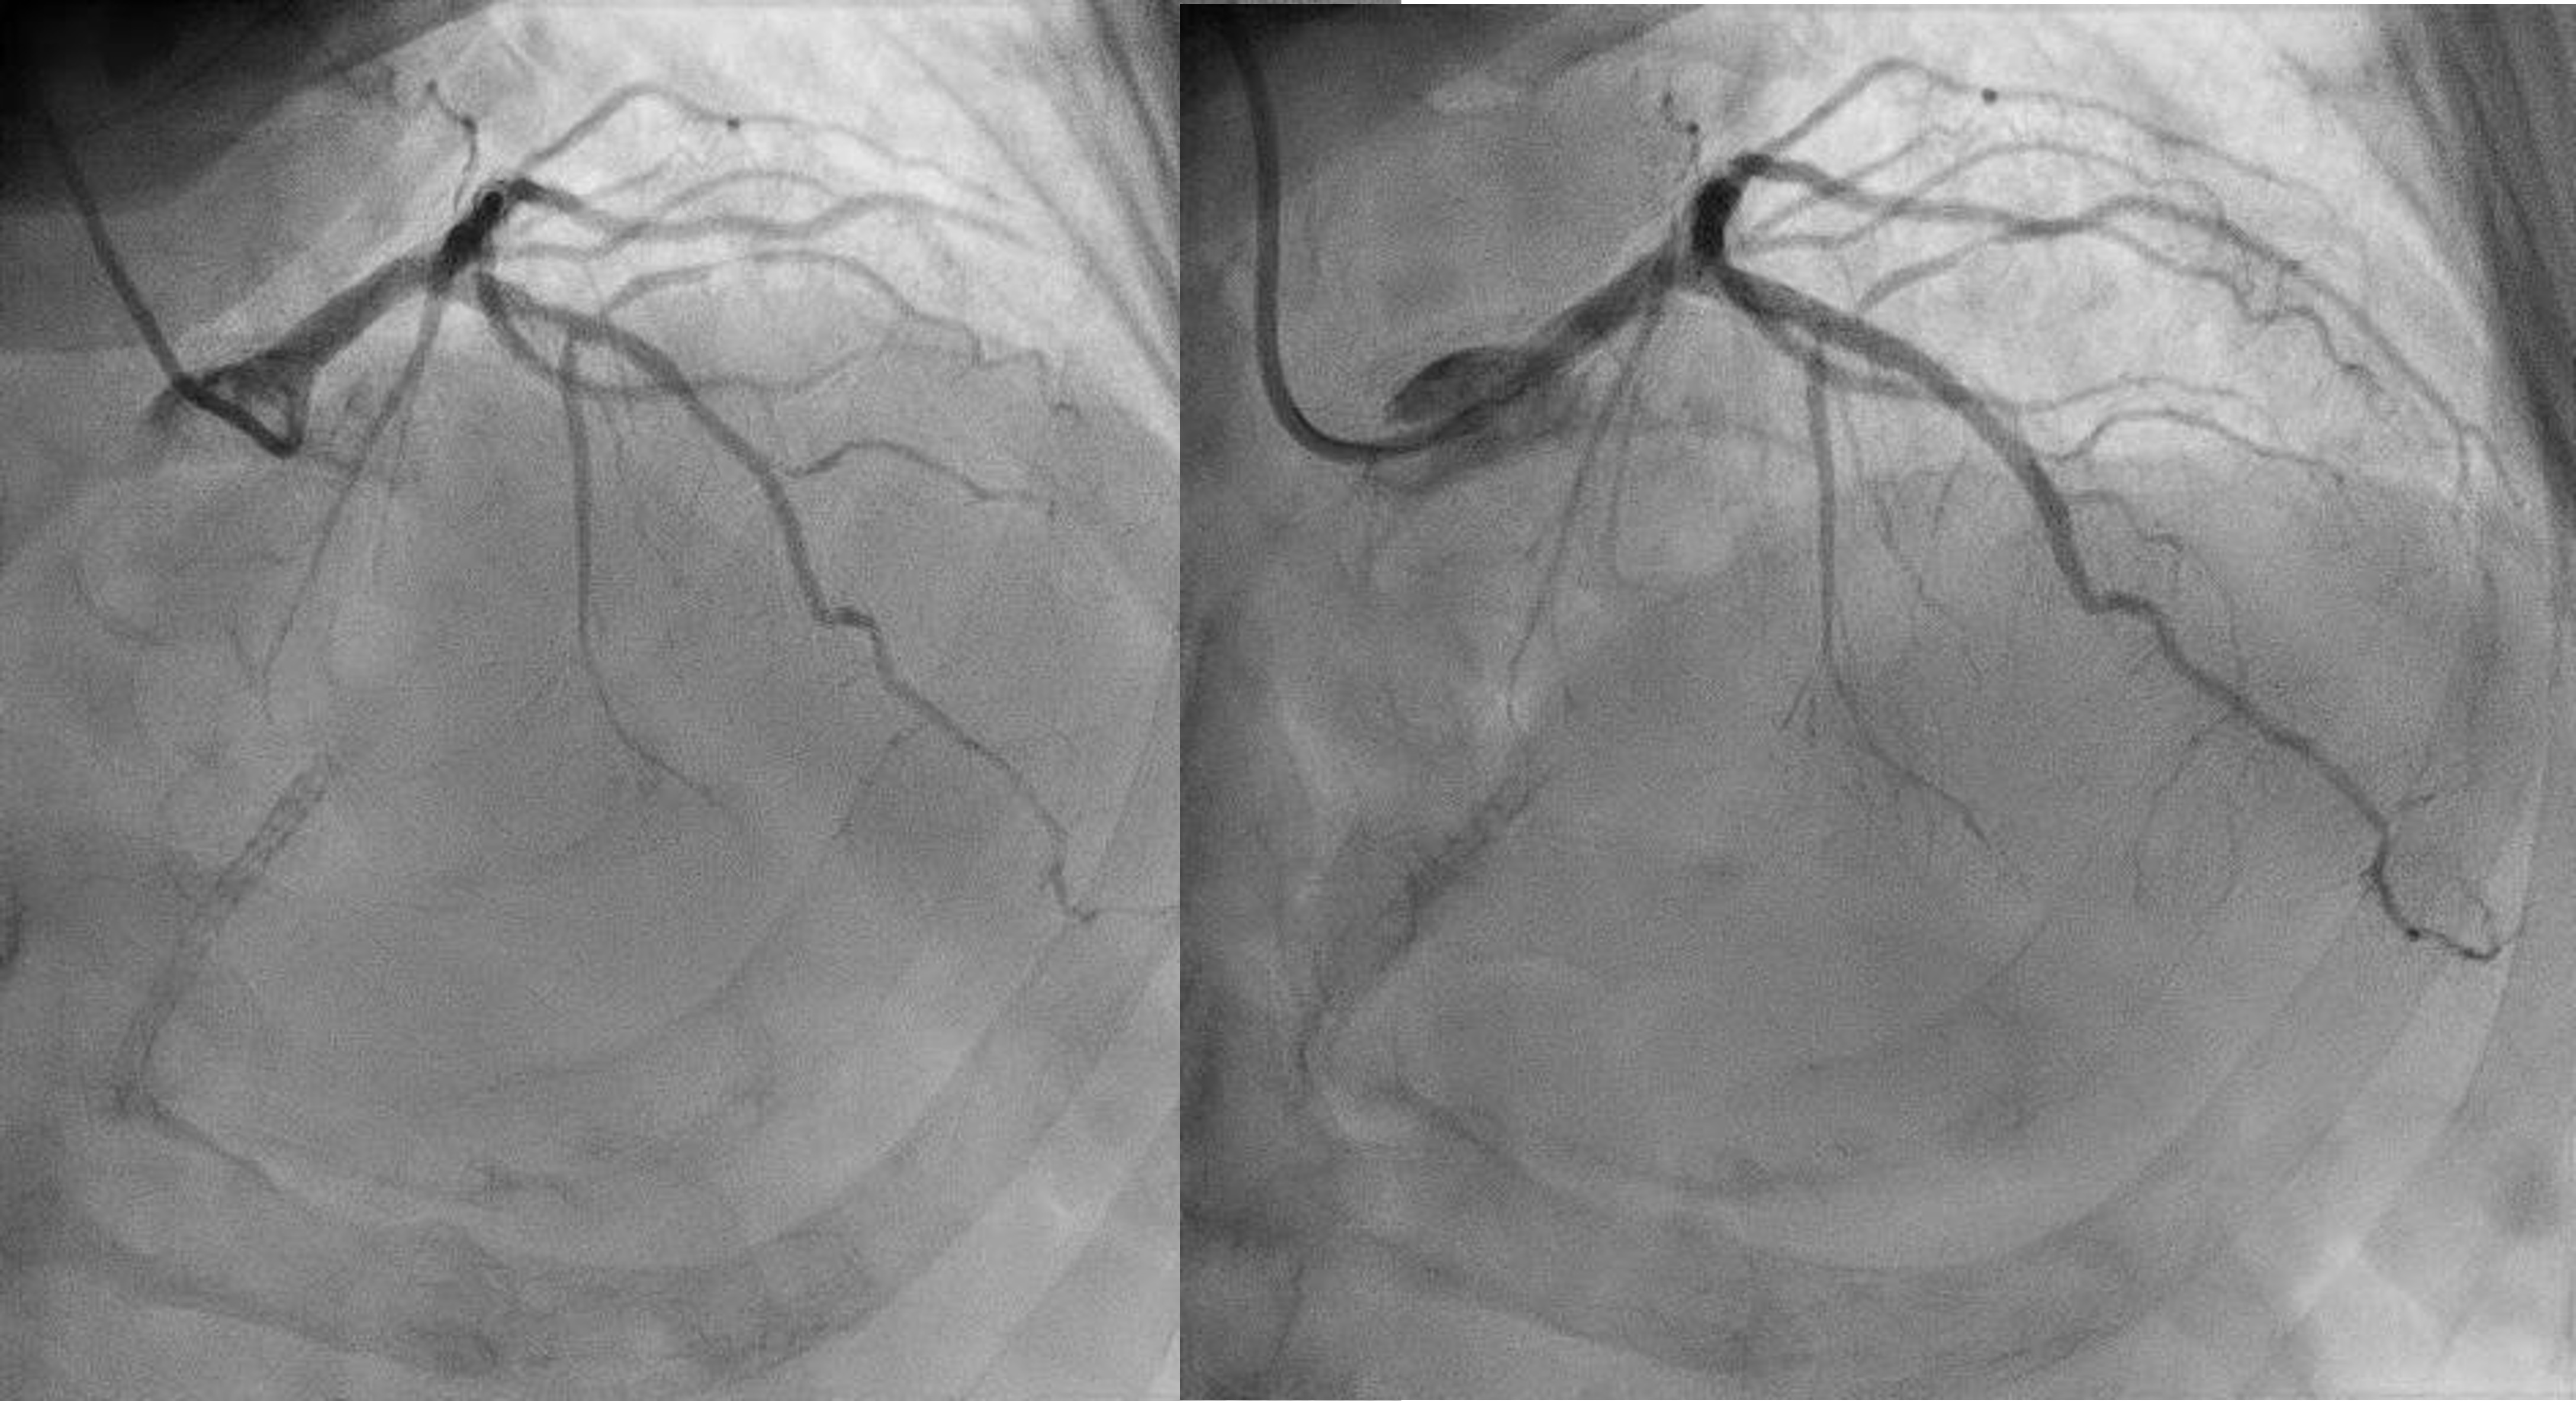

ECG showed sinus rhythm. 24hours ECG ( Holter ) showed ectopics < 1% , pause < 2secs [not significant].Echo showed EF 45-50% with hypokinesia (as shown above) – no thrombus or severe aortic stenosis. Creatinine was ~130umol/L ( not markedly raised).Ad hoc Coronary Angiography was performed:LM <30% stenosesLAD Prox 70-80%LCx ISR (Prox-Mid) 80-90%RCA ISR (Pros) 80% , DominantPCI to LCx ISR – DEB 2.75/20mm , PCI to LAD (ostium-mid) – DES 2.75/33mm + 3.5/13mm

Relevant Catheterization Findings

Now for staged PCI to RCA. Attempted engagement with a JR 3.5 6Fr via RRA.Challenges anticipated:1 subclavian tortuosity, noted from past angiography – needing gentle manipulation, avoid femoral access2 poor engagement due to ostium disease3 wiring from outside ( ¡®air-mail¡¯)Lesions are calcifed, diffuse, proximal(ostium RCA) and distal to stented segment - stent not covering ostium.Plan is to IVUS, prepare new lesions, prepare ISR segments then either hybrid DES/DEB or new DES all the way.